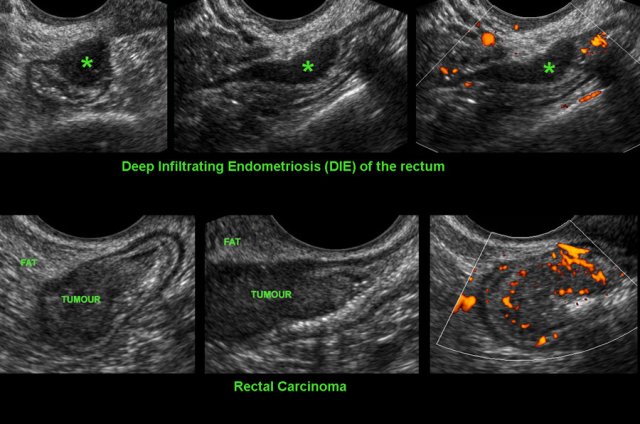

Differentiating DIE from carcinoma

Differentiating rectal cancer from DIE of the rectum.

Both conditions appear as solid, moderately defined, rather hypoechoic, asymmetrically localized masses arising from the rectum with a tendency to narrow the lumen. TVUS may be key to discriminate the two.

In DIE the hypoechoic mass is hypovascular, it is localized at the outer contour of the rectum and is continuous with the hypoechoic muscularis. The submucosa and mucosa of the colon are intact.

In rectal CA, the hypoechoic mass is hypervascular and the mass originates from the mucosa, with focal loss of layer structure as a consequence of transmural tumour growth.